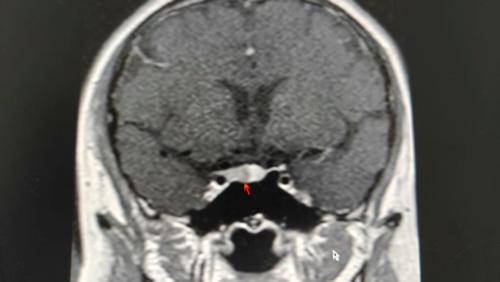

为查清病因,李女士住院治疗,王敏主任医师带领医疗团队开始了缜密的诊断过程,最终诊断指向ACTH依赖性库欣综合征——垂体ACTH瘤,该病的患者因ACTH过度分泌引发皮质醇增多症,典型症状包括向心性肥胖、满月脸、皮肤紫纹及代谢异常,可合并糖尿病、性腺功能抑制等并发症。由于肿瘤体积微小(通常直径毫米),CT及MRI(核磁共振)检出率较低,诊断主要依赖内分泌学检查。